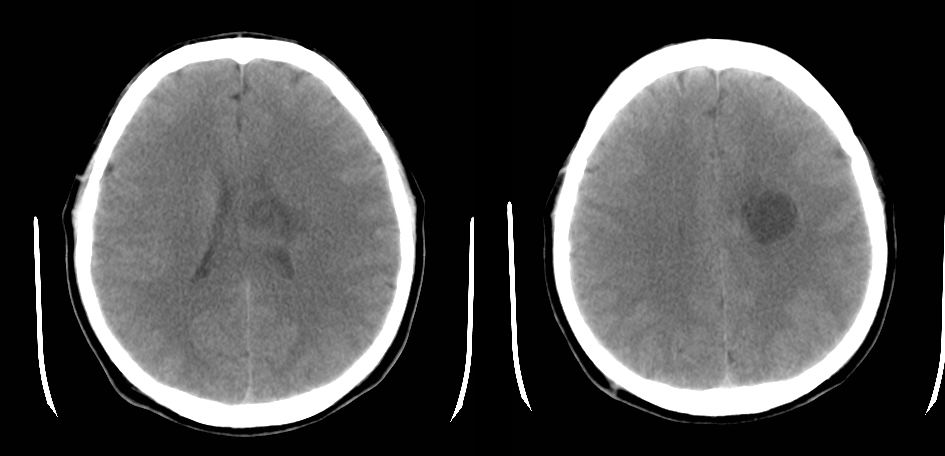

以下是引用zyx168在2007-9-1 7:00:00的发言:[br]首先考虑脑脓肿。此例从影像与临床很难鉴别:胶质瘤,囊虫病,转移瘤。

以下是引用zjzjr在2007-8-31 22:26:00的发言:[br]病灶呈薄壁环形强化,未见壁结节,支持脑脓肿可能性大.

以下是引用liuhongjun01在2007-9-1 11:12:00的发言:[br]病灶呈囊状有轻度占位,增强后呈环形薄壁强化,没有明显壁结节影,病灶位于半卵圆中心,[br]与硬脑膜无关系,考虑慢性脑脓肿,请结合临床,须与脑囊虫病、肿瘤等鉴别,单凭影像难肯定诊断。